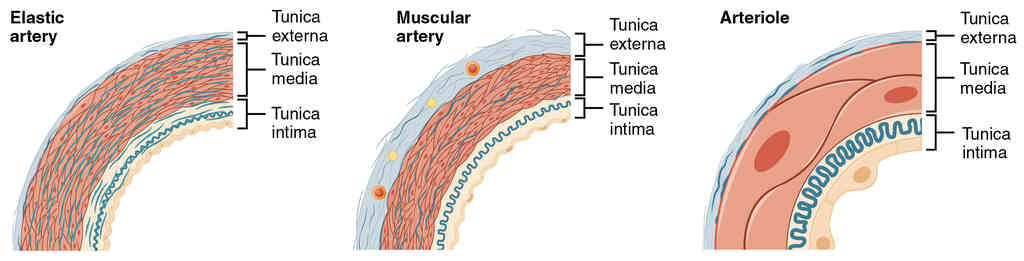

This page is under construction. For now, it is just a resource of the images found in the OpenStax Anatomy and Physiology Handbook. It wil slowly change into a revision tool. Each slide has a number. Use this to refer to the slide. When completed, it will have an unlabelled section, with labelled slides in parallel. On the unlabelled slides, write your answer and use the labelled slide to assess yourself. Keep track by also noting the number on each slide. Improvement at each attempt is important, more so than full marks on a first attempt.